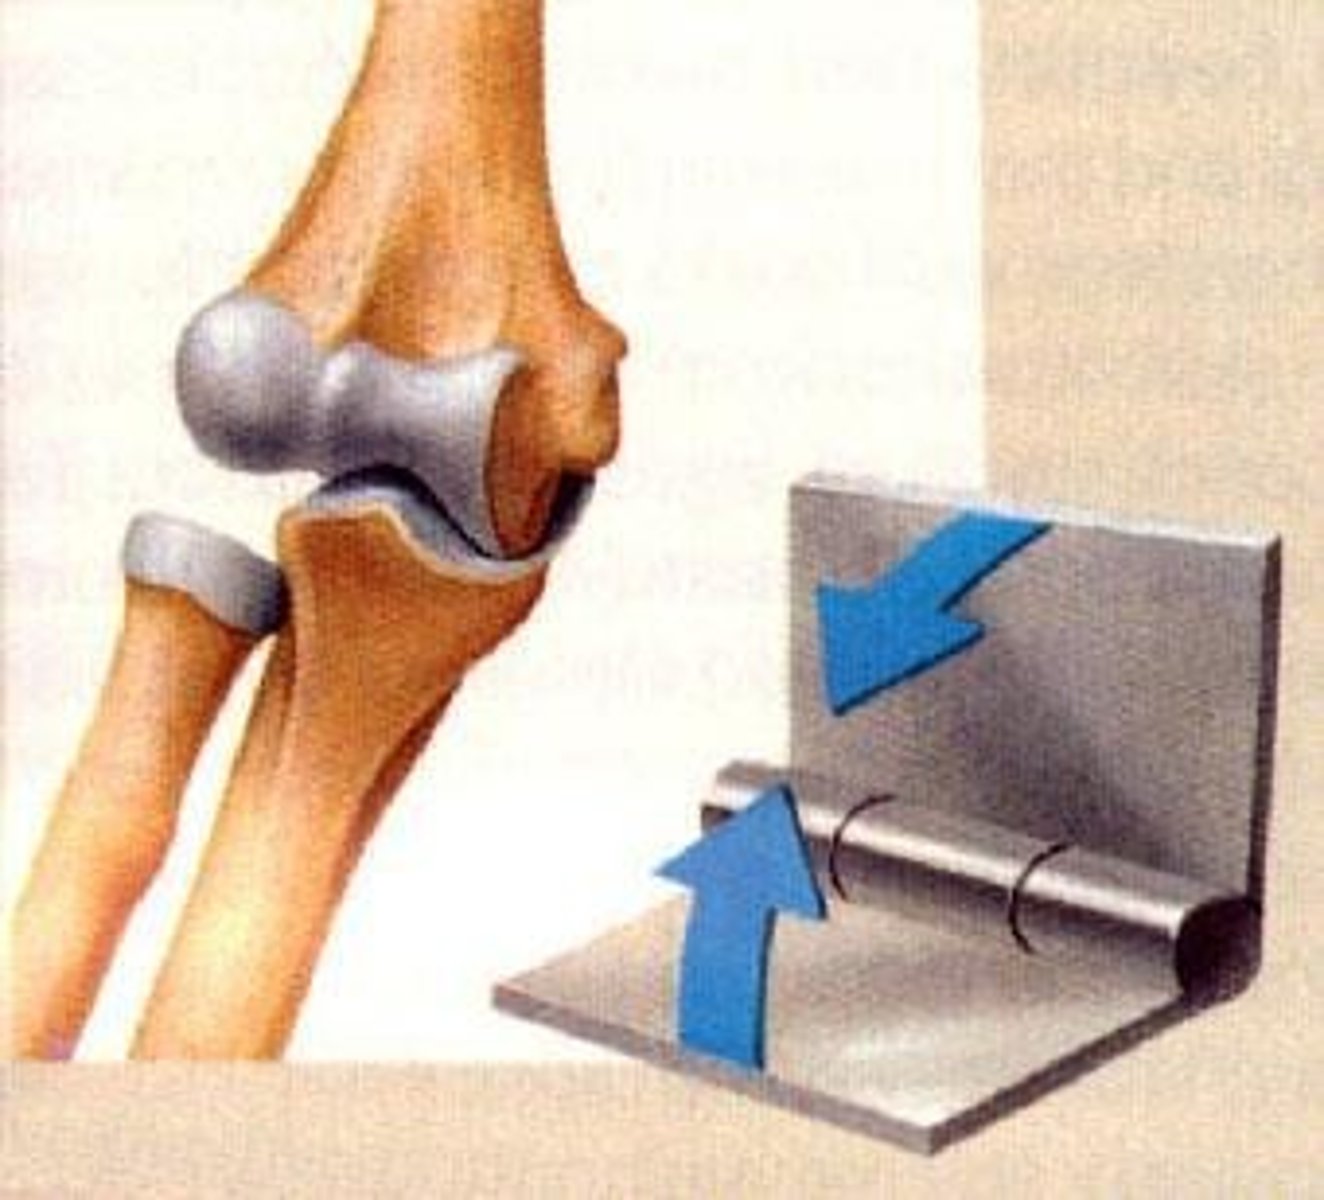

Hinge Joint

<p>permit movement only in one plane, e.g., elbow; knee</p>